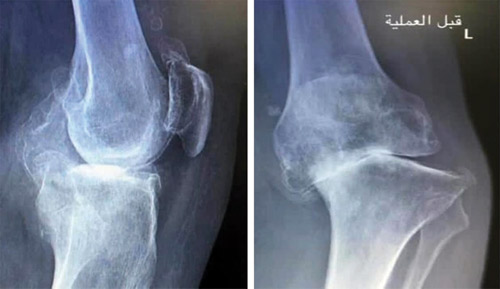

وقال البروفيسور فوزي بن فهد الجاسر أستاذ واستشاري جراحة العظام والمفاصل رئيس الفريق الطبي المعالج، إن المريض راجع المستشفى في الأسبوع الأول من شهر شعبان الجاري، مشتكياً من آلام حادة ومزمنة في مفصل الركبة اليسرى، وعدم القدرة على الحركة، وبعد الكشف السريري والاطلاع على التاريخ المرضي، أجريت له صور أشعة سينية بيَّنت وجود خشونة متقدمة في مفصل الركبة وتقوّس حاد بالساق إلى الداخل، فأخُضع المريض بعد اتخاذ الترتيبات والتحضيرات اللازمة لعملية مزدوجة، الأولى تم فيها استبدال مفصل الركبة اليسرى بأحدث التقنيات، وفي الثانية زرع الفريق الطبي دعامة في الساق، وذلك لعلاج التقوّس، وضمان استقرار المفصل الجديد، وتكلَّلت العملية التي استمرت زهاء الساعتين بنجاح تام الحمد لله، وقد اتخذ الفريق الطبي الإجراءات الطبية اللازمة لتخفيف الألم إلى أدنى مستوى عبر تقنيات تحديد مواضع التخدير بدقة، وكذلك تقليل احتمالات حدوث أي التهابات بعد العملية.